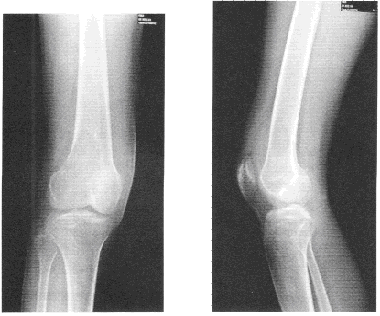

患者男,24岁。右膝疼痛3个月。患者3个月前无明显诱因出现右膝部疼痛,1个月前疼痛加重,伴膝关节外侧肿胀。拍片示股骨下端骨破坏。无发热等全身症状,既往无外伤史。查体:右膝关节外侧轻度肿胀,皮肤不红,压痛明显,膝关节活动正常。血常规和血生化检查正常。右膝关节X线平片正侧位片,如图。

首先考虑的诊断是()